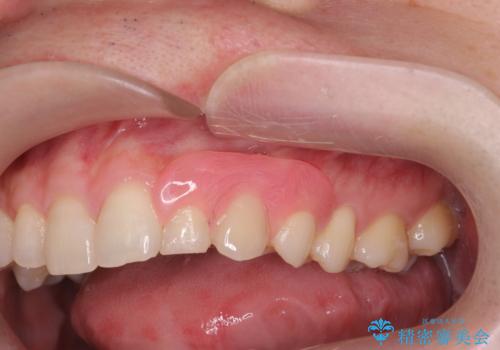

型取りと装着の2回で治療を終了することができました。

- 慣れるまで微調整で何度か通って頂くことがあります

- 就寝時や食後に毎回取り外して、清掃する必要があります